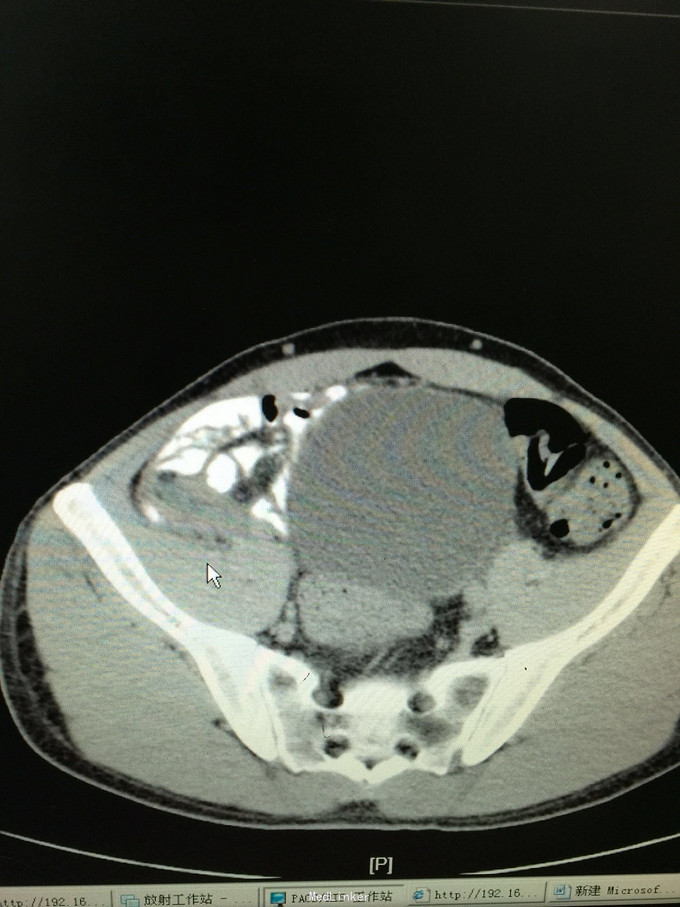

42岁男患,转移性右下腹痛5天为主诉入院。 患者5天前无明显诱因出现中上腹部疼痛,继而转移为右下腹部疼痛,呈持续性绞痛,发热最高体温38.4摄氏度,无恶心呕吐,无寒战,排气排便正常,自行给予口服抗炎药物治疗后发热缓解,腹部疼痛症状缓解不明显,并有加重趋势来诊。门诊查彩超示阑尾炎伴周围脓肿,并收入院治疗。既往发现乙型肝炎肝硬化3年。家族遗传性乙肝

查体:各生命体征正常,心肺无异常,腹部查体:腹平坦,未见腹壁静脉曲张,腹软,未见胃肠型及蠕动波,右下腹可触及一质韧包块,大小约5✖️3cm,界限欠清,活动度一般,右下腹压痛阳性,反跳痛弱阳性,无肌紧张,以麦氏点压痛为重。 辅助检查:详见图片

诊断:急性阑尾炎伴阑尾周围脓肿,乙肝肝硬化 处理:患者入院后经查无腹膜炎体征,经上级医师查看后指示患者阑尾炎伴周围脓肿形成,存在手术相对禁忌,无手术绝对指证,建议给予积极抗炎对症治疗,患者肝炎肝硬化,注意各理化指标变化,积极复查。